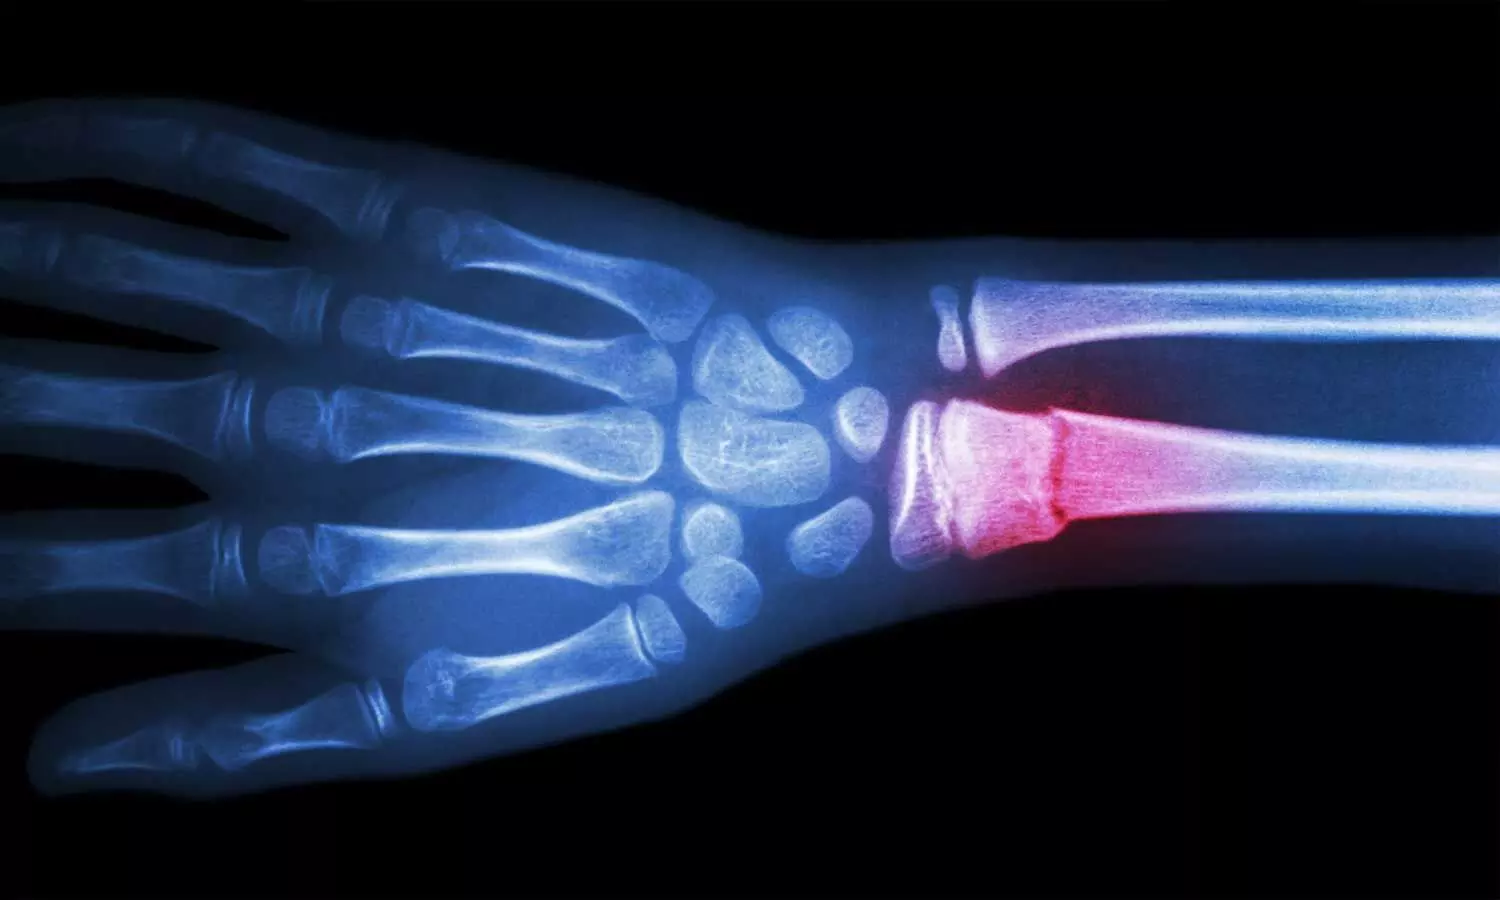

Bone abnormalities encompass a diverse range of conditions affecting the skeletal system, leading to structural changes, deformities, or impairments in bone development or density. These abnormalities may arise due to congenital factors, injuries, metabolic disorders, or genetic predispositions.

2. Orthopedic Interventions: Surgical procedures to correct deformities, stabilize fractures, or repair bone abnormalities.